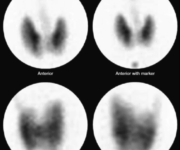

Un altro strumento diagnostico importante, sebbene utilizzato in casi selezionati, è la scintimammografia con Tc-99m Sestamibi (MIBI). Questo esame viene proposto quando la mammografia tradizionale, specialmente in seni con tessuto molto denso, fornisce risultati dubbi o non conclusivi. La procedura è semplice e prevede l’iniezione endovenosa del radiofarmaco, seguita dall’acquisizione di immagini delle mammelle. Le cellule tumorali maligne, caratterizzate da un alto metabolismo e da una densità mitocondriale elevata, tendono ad accumulare il Tc-99m Sestamibi in modo significativo. Pertanto, la presenza di un’area di ipercaptazione (“hot spot“) può indicare la natura sospetta della lesione, guidando il medico verso una biopsia mirata.